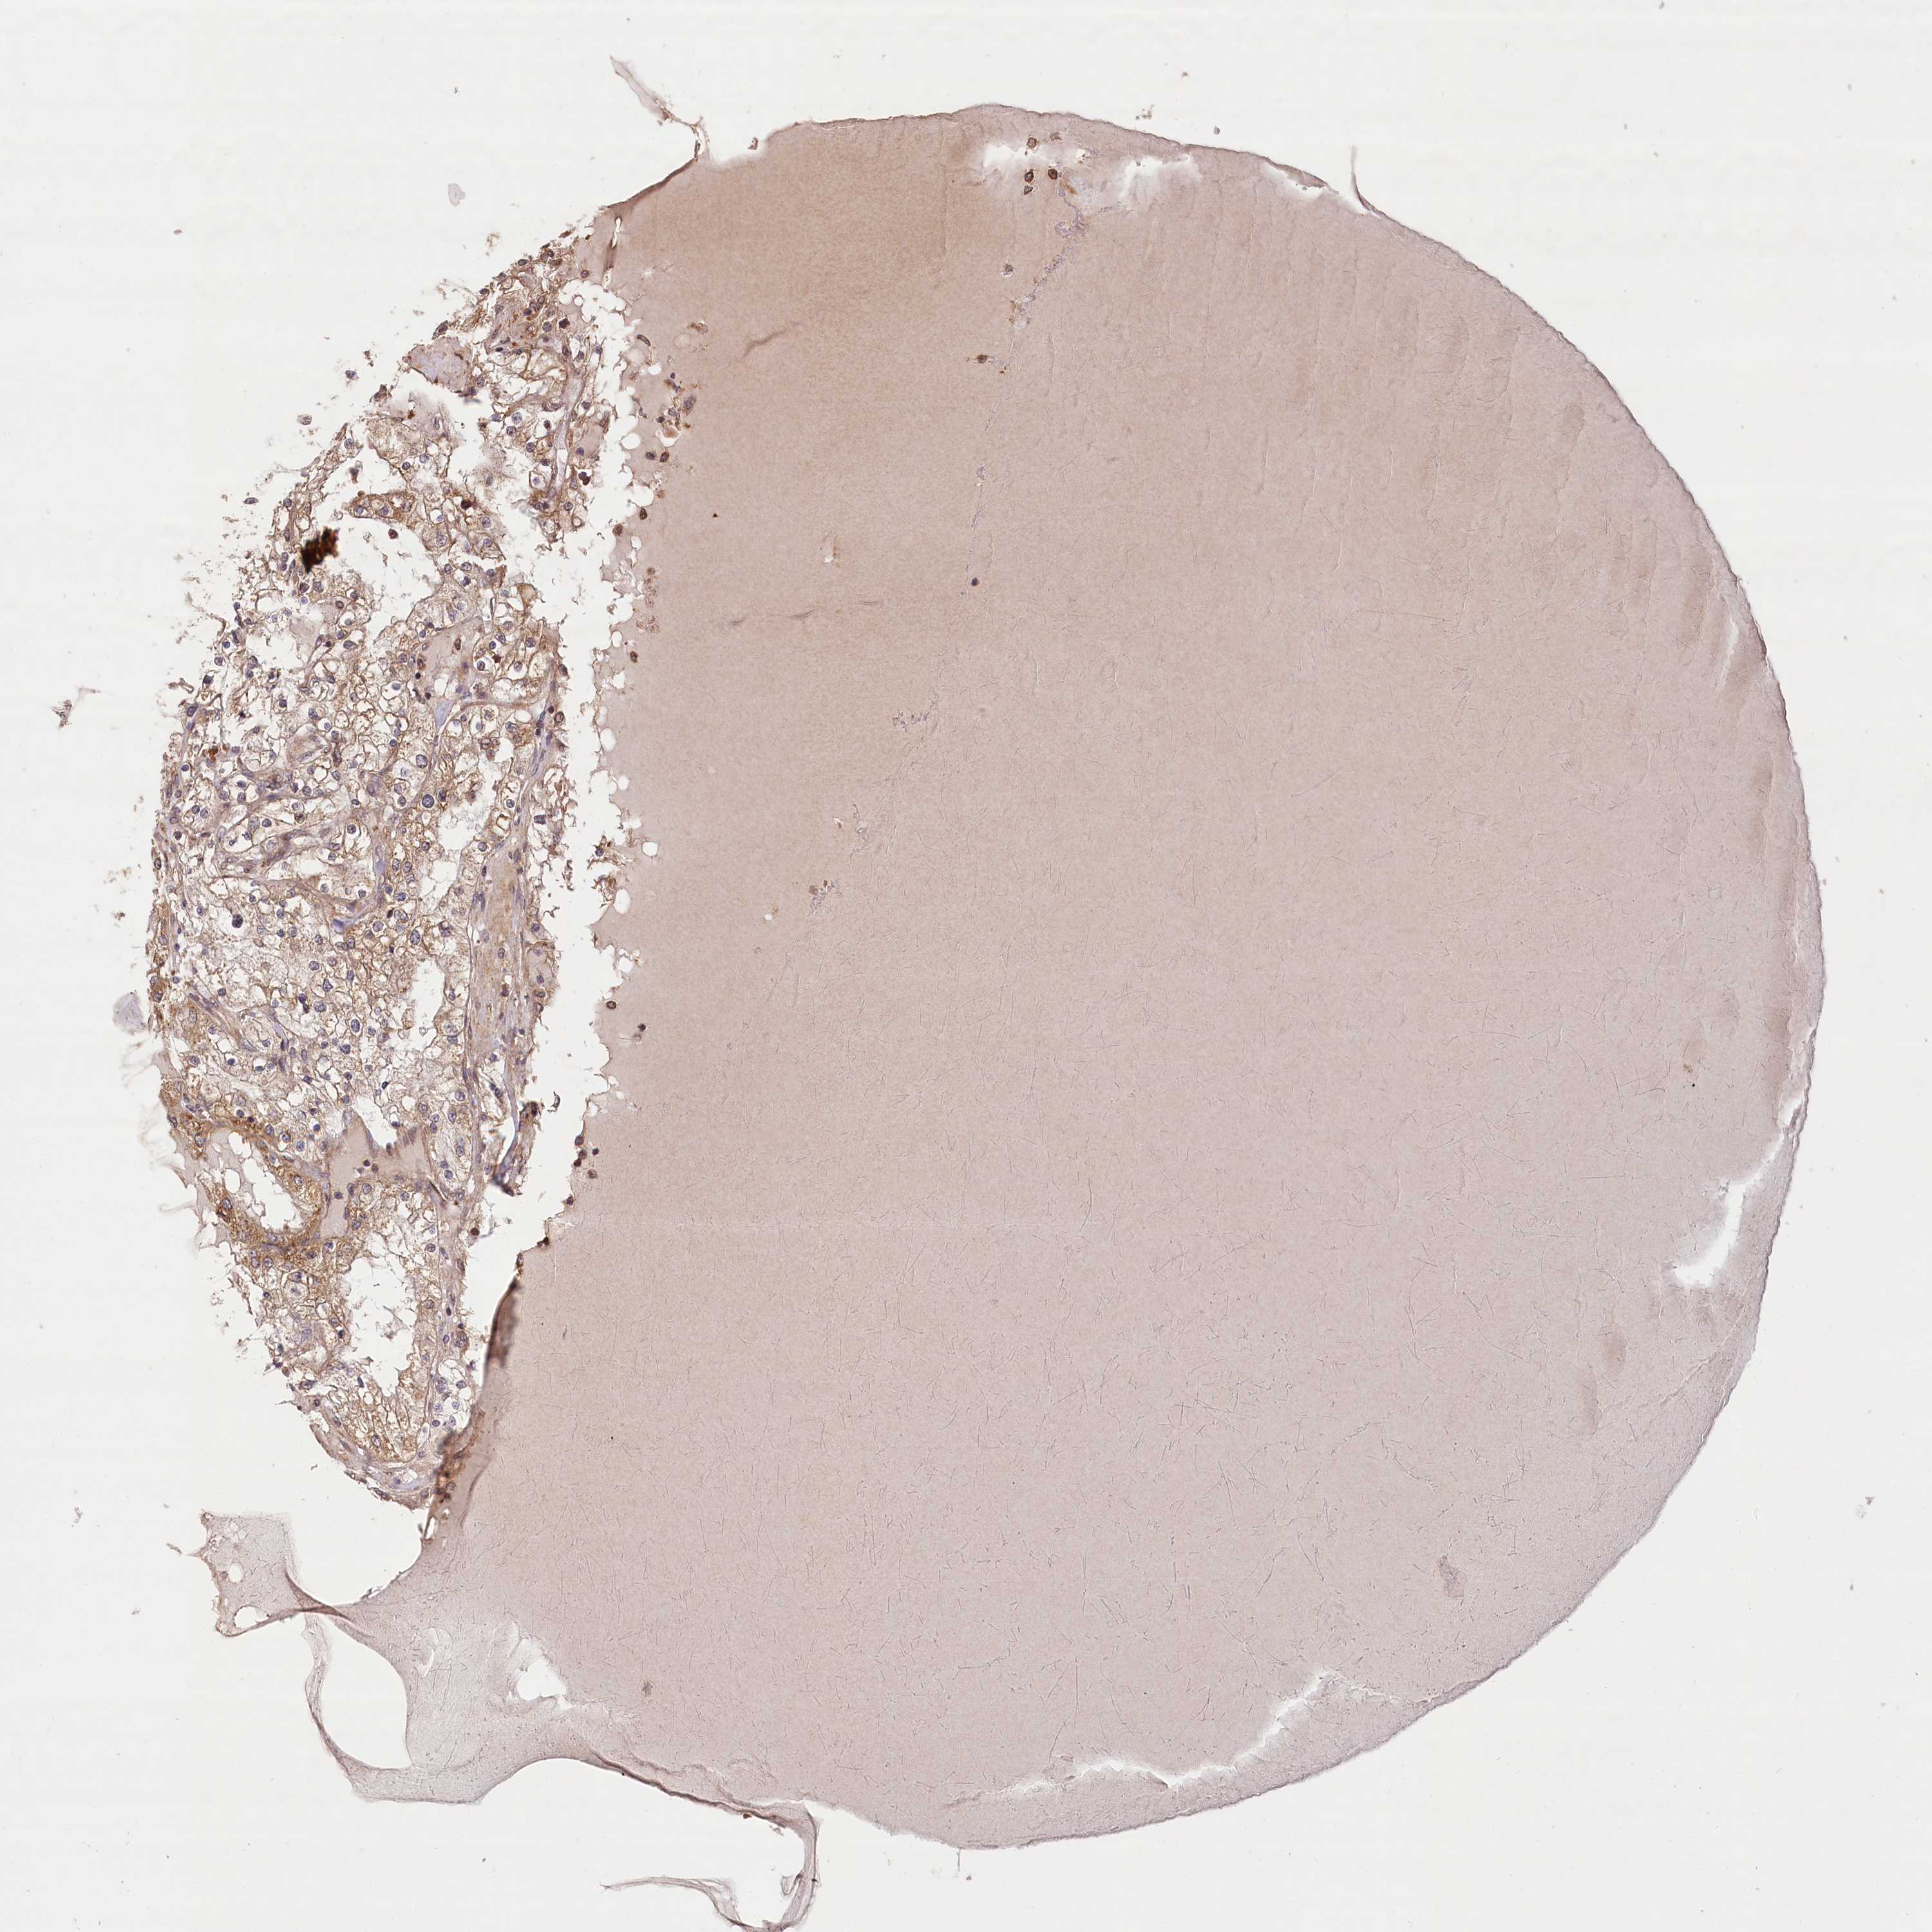

KIDNEY RENAL CLEAR CELL CARCINOMA (VALIDATION) - Interactive survival scatter ploti

LSS is not prognostic in Kidney Renal Clear Cell Carcinoma (validation)

Best expression cut offi

When clicking on this number, the vertical dashed line indicating cut-off, the interactive survival plot, and the Kaplan-Meier curve will be adjusted to show results based on the best expression cut-off.

: 7.68

P scorei

N/A

5-year survival highi

5-year survival lowi

Average pTPM 10.1

Number of samples 100